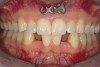

Figure 2c  One week postsurgery with mesial buildups on Nos. 5 and 12 and thin pontics on archwire to conceal spaces during closure.

Figure 2c

Figure 2d  Prerestorative orthodontics was completed in 5 months. Final result 3 years, 4 months after completion.

Figure 2d